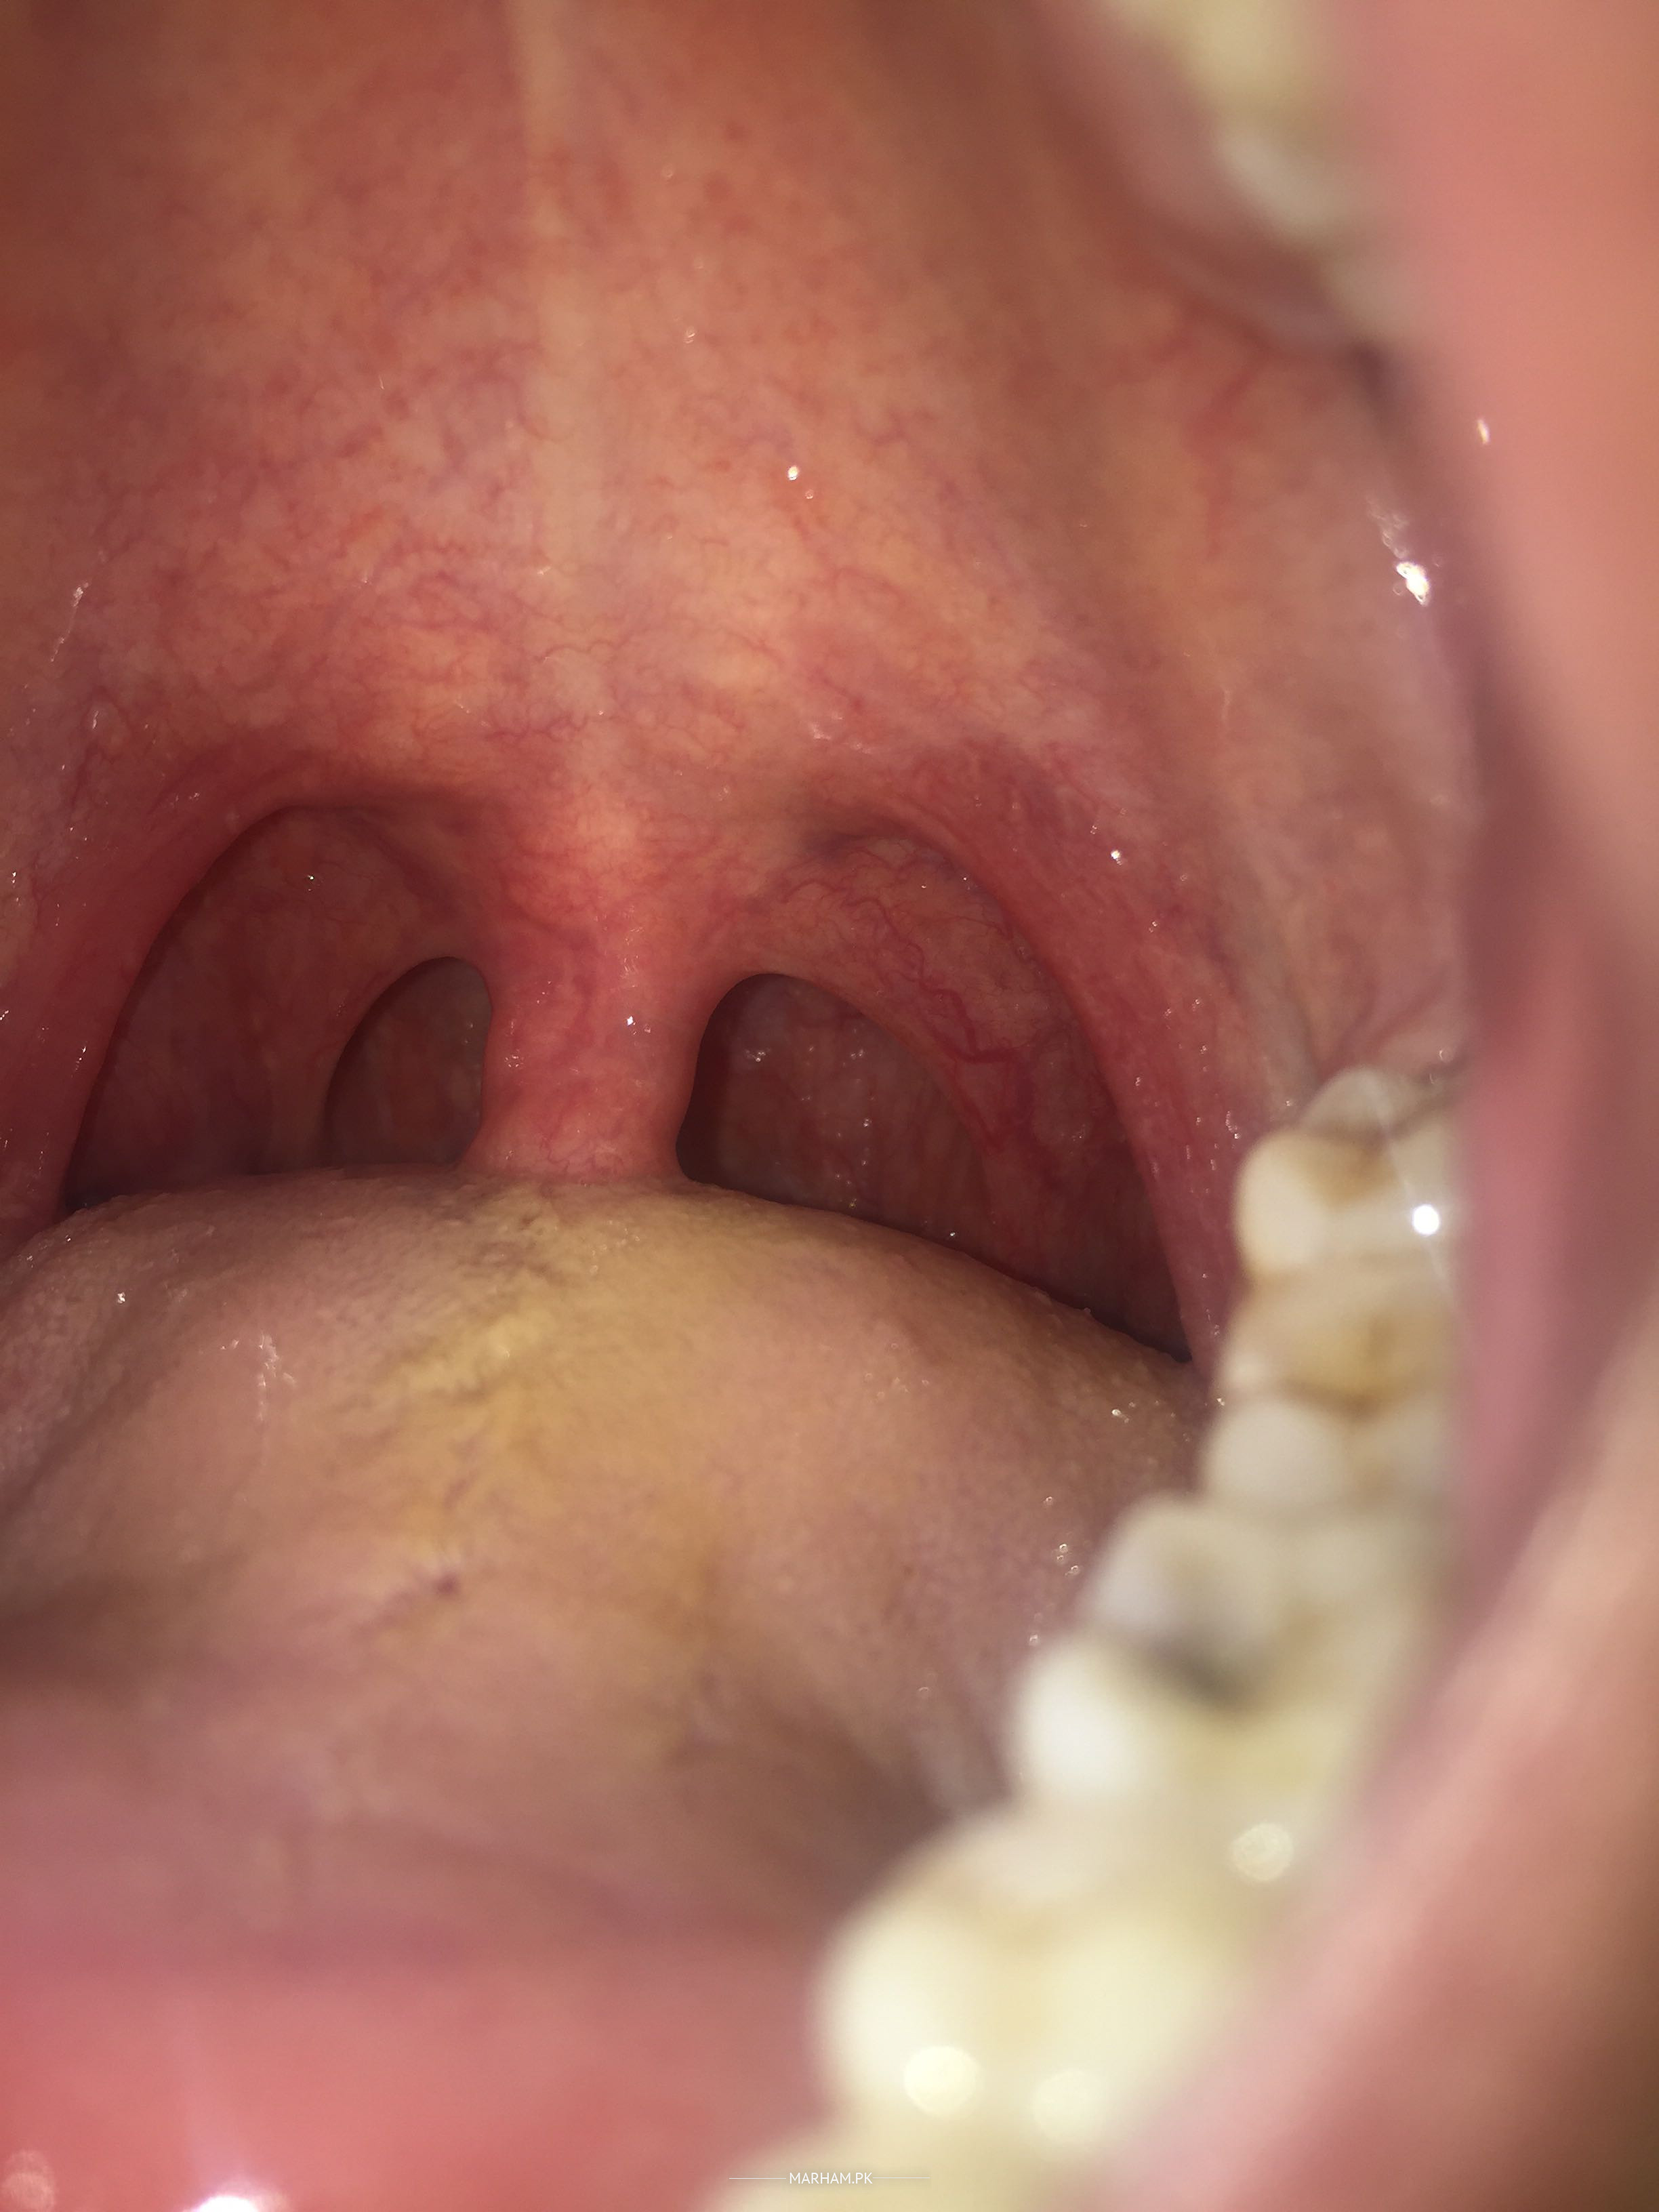

It has been more than 2 weeks since my throat hurts, small white pimples are present at the back of my neck, i did consult several doctors in quetta as well as on this app but the problem still wont go away...

Hello and GOOD evening Any blood tests?????Seems to be viral infection,  one side of throat is more . Brexin once daily. Tab. Lorin NSA once daily Tab. AZOMAX 500mg once daily  1hour before meal. Enziclor mouth wash Gargles three times a day.

The doctor i visited in Quetta also said that it is an infection, i do feel more pain on the right side of the throat and ear, i have been taking Amclav(1g), Metrozine and gargle with salt for more than two weeks but it has not shown any improvement